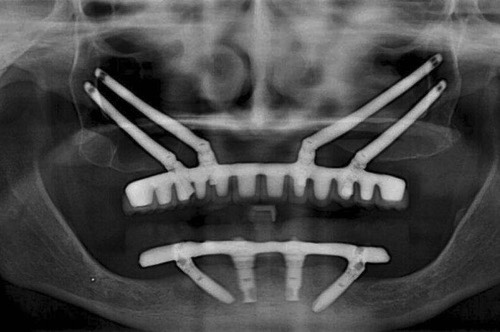

穿颧种植牙是上颌骨严重骨吸收情况下的一种有效替代治疗方法,也可被用于上颌骨缺损的修复治疗,既避免了大量的植骨手术,且能明显缩短种植治疗周期。

效果展示

手术方式

1. 骨量充足的 1 区及双侧缺骨的 2、3 区:建议 2-4 颗传统轴向种植体位于 1 区,双侧 2 或 3 区各加一颗颧骨种植体。

2. 骨量充足的 1 区及一侧缺骨的 2、3 区:建议缺骨侧 2、3 区一颗颧骨种植体,对侧 2、3 区及 1 区采用常规种植体。

3. 缺骨的 1 区及骨量充足的 2、3 区:一颗颧骨前种植体加后方常规种植体即可。

4. 1、2、3 区均缺骨:4 颗颧骨种植体即可。

项目优点

避免取骨、植骨等附加手术,而且种植当天可以短时间戴固定牙,能实现即刻负重,大大缩短了治疗时间。是上颌骨重度骨吸收情况下的一种有效替代治疗方法,也可被用于上颌骨缺损的修复治疗,既避免了大量的植骨手术,且能明显缩短种植治疗周期。